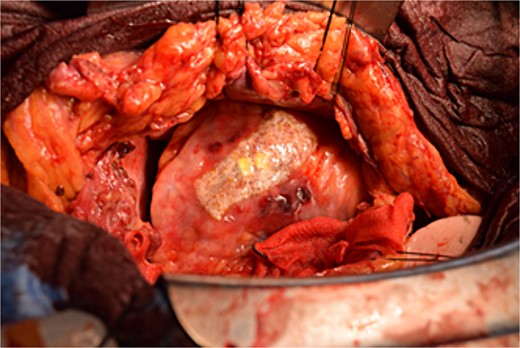

Immediately prior to surgery, he suffered cardiac arrest requiring cardiopulmonary resuscitation but recovered quickly, and a median sternotomy was performed expeditiously. Fortunately, no injury to the retrosternal gastric tube occurred. The gastric tube was pushed into the right thorax to expose the pericardial surface. A pericardial hematoma was observed, and pericardiotomy relieved the tamponade. Removal of the hematoma revealed a 5 mm aneurysm in the peripheral right ventricular branch with pulsatile bleeding (Fig. 4). Hemostasis was achieved using horizontal mattress suturing between the central and peripheral areas of the aneurysm without bypass grafting to the right ventricular branch artery by cardiac surgeon. In addition, TacoSeal® (CSL Behring, Pennsylvania, USA) and Volheal® (KM Biologics, Kumamoto City, Japan) were applied (Fig. 5). The operative time was 133 min, with a blood loss of 1160 ml. Oral intake was initiated on POD 5, and the patient was discharged on POD 22 with an unremarkable postoperative course.

A 5 mm aneurysm in the peripheral right ventricular branch with pulsatile bleeding is observed.